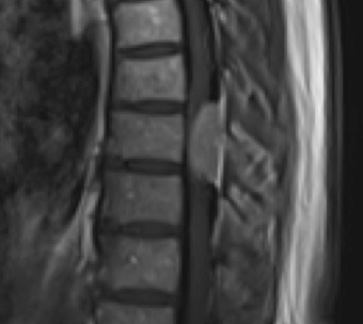

Preoperative MRI T1w demonstrating a large enhancing tumor (red arrow) causing severe cord compression and displacement (blue arrow)

Preoperative MRI T2 demonstrating obstruction of CSF around the cord (blue arrow), resulting from the tumor (red arrow)

This is a 55-year-old female with no past medical history who presented electively with a 10 month history of progressively worsening mid back pain radiating across the chest, and gait disturbance. Pain was especially worse at night and when laying flat. Her exam was pertinent for severe ataxia when ambulating, and elevated deep tendon reflexes in the lower extremities. She had severe and debilitating symptoms, as demonstrated by her Visual Analog Scale (VAS) and Oswestry Disability Index (ODI) of 9/10 and 64/100, respectively. MRI of the thoracic spine with and without contrast demonstrated a large intradural extramedullary homogenously enhancing mass at T8, resulting in near obliteration of the spinal canal and severe cord compression. She was referred to Dr. Xavier Gaudin for neurosurgical management.